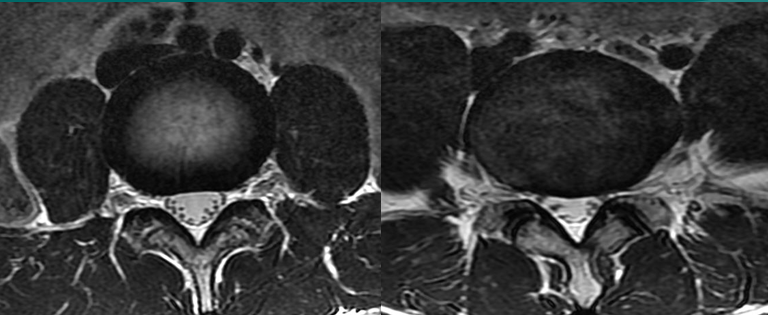

一个健康的45岁男性的L4椎间盘的轴状面观。

髓核区及周围的纤椎环区。

靠近L5神经根的椎间盘后缘的凹度,这是正常健康椎间盘的象征。

L4发出神经根更靠侧方一点。这就不难理解为什么如果有大的椎间盘突出或椎管狭窄,发出神经根L4及过往神经根L5将同时受压。

在此图中,可清楚地看到悬挂在硬膜囊内的细小的神经根(L5神经根及S1神经根),它们以不完全有绪地状态排列着。注意,神经孔是很开阔的(浅黄色区),表明没有因邻近椎间关节问题形成在的椎管狭窄。T2加权象对于察看退化性椎间盘病是最好的,因为T2像将富含水份的结构表现为亮白色, 含水少的区域表现为黑色。

位于椎体之间的椎间盘应是白色的(含水多)。注意黑颜色(脱水的)的L5椎间盘(L5与骶骨之间的椎间盘),这代表了中度到重度的退化性椎间盘病。